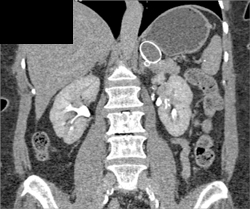

Accessory Spleen Vs Islet Cell